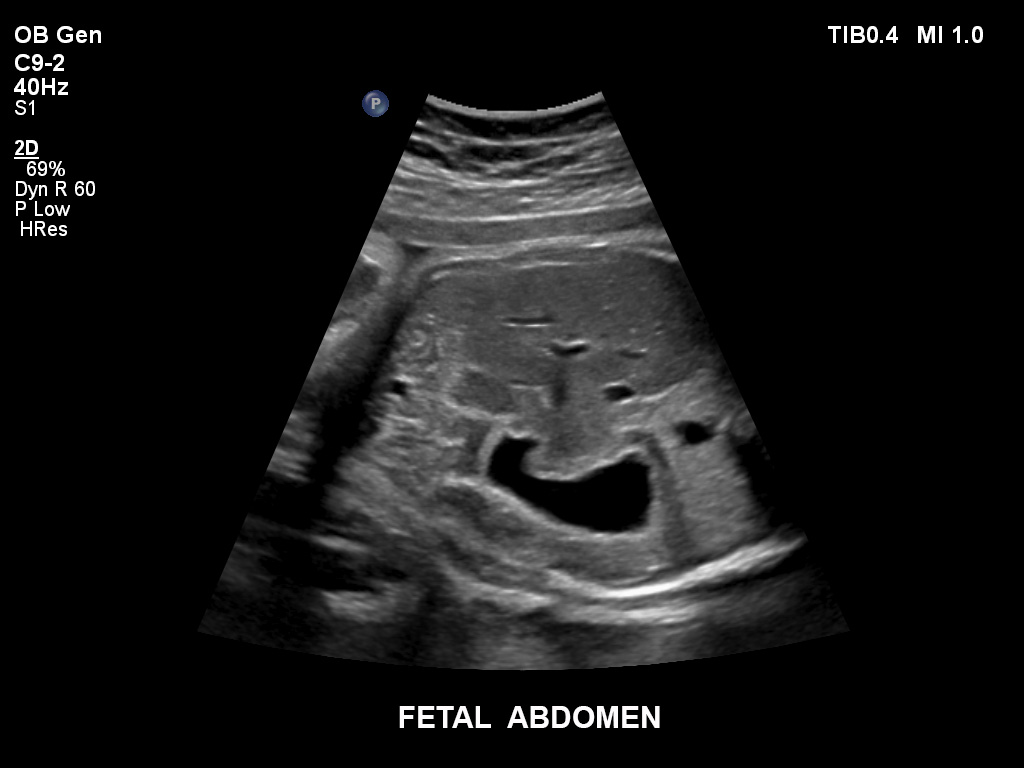

Die EPIQ-Produktreihe mit ausgereiften Schallköpfen erfüllt die Anforderungen auch Ihrer anspruchsvollsten gynäkologischen Untersuchungen und während der gesamten Schwangerschaft.

• C9-2 PureWave-Breitband-Convex-Schallkopf für Hochfrequenz-Bildgebung in der Gynäkologie und der Geburtshilfe, insbesondere für die Untersuchung im Hinblick auf mögliche Anomalien im ersten Schwangerschaftstrimester

• C5-1 PureWave-Breitband-Convex-Schallkopf für hohe Eindringtiefen in der Gynäkologie und der Geburtshilfe, für Patientinnen mit Schwangerschaftsdiabetes oder vorzeitigem Blasensprung